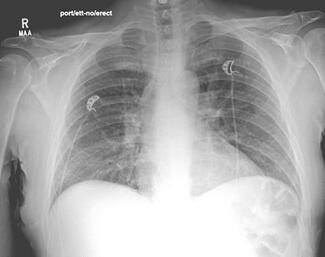

Here the authors present a case of a 46-year-old male patient admitted with a localized necrotizing soft tissue infection of the right foot that developed unusual and rare delayed hypersensitivity pneumonitis from the antibiotic...